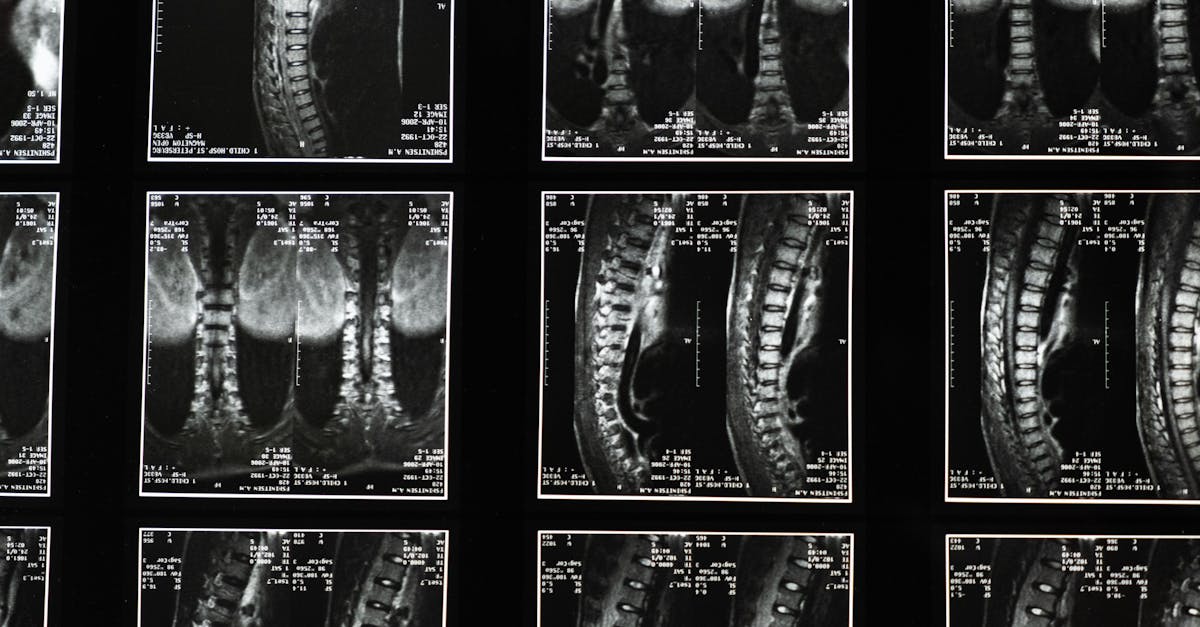

Patients in Saint-Jérôme are encouraged to undergo detailed evaluations, including MRI and CT scans, to confirm the extent and nature of disc herniation. Dr. Sylvain Desforges employs a comprehensive assessment protocol at the DiscRelief Clinic, leveraging advanced imaging coupled with clinical expertise to map precise nerve involvement and tailor patient-centric strategies.